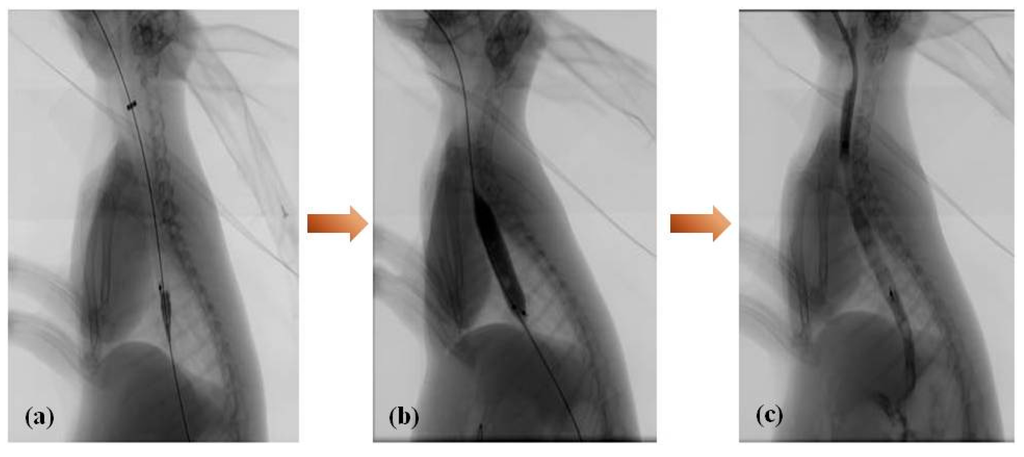

Stenting was successful in all 10 rabbits in the magnesium-(PCL-PTMC) stent group. All rabbits tolerated the procedure well and procedure-related adverse events, including esophageal perforation and bleeding, did not occur during or following stent insertion. Esophagography revealed that the contrast agent passed smoothly through the stented esophagus in both groups (Figure 5). No immediate stent migration into the stomach occurred after stent placement in the magnesium-(PCL-PTMC) stent group.

Figure 5. Esophagography during stent insertion (a); balloon dilation after magnesium-(PCL-PTMC) stent insertion (b) and immediate esophagogram (c) reveals that the stented esophagus is well patent.

The magnesium-(PCL-PTMC) stents were placed in the lower third of the esophagus of the rabbits in the stent group. A stiff exchange wire (0.035 in × 260 cm, diameter × length, Terumo, Tokyo, Japan) was threaded through the mouth and into the stomach under fluoroscopic guidance. This wire was used as a guide to deliver the stent into the lower third of the esophagus. Using fluoroscopic guidance and esophagographic images, the stent was released. To achieve full expansion, a balloon catheter (10 mm × 40 mm) was inflated within the stent. Further esophagography was done to verify the extent of stent expansion and esophageal perforation. Rabbits from the control group did not receive a stent.

Pneumatic Dilation Procedure

The 75-cm-in-length (Changhong Medical Instrument Co., Ltd., Changzhou, China) balloon catheters (10 mm × 40 mm) were used in this study. All the rabbits were fixed in the supine position. After a 260-cm-long stiff exchange wire (Terumo, Tokyo, Japan) was passed through the esophageal and into the gastric cavity, the balloon catheter was advanced over the guide wire and positioned across the diaphragmatic hiatus using radiopaque markers as a guide. The balloon was then inflated for 10 to 20 s until the stents was expanded. After the stent’s dilation a transcatheter gastrograffin injection was performed right now to prevent the occurrence of esophageal perforation.